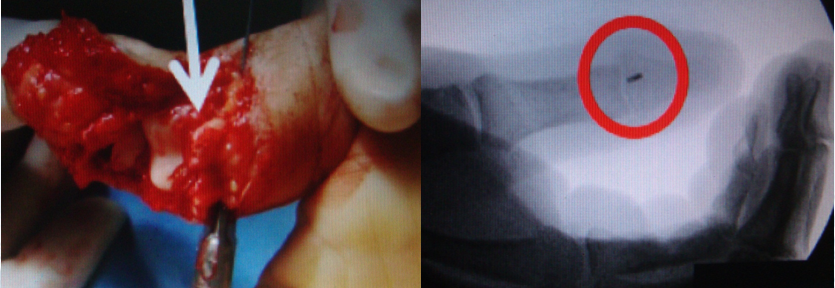

2.带线锚钉治疗跟腱止点撕脱

跟腱止点撕脱:当跟腱断裂部位距离止点小于2 em时,可视为跟腱近止点断裂。由于腱性组织至骨面止点逐渐移行为菲薄的结缔组织结构,其特点为组织菲薄、血运较差、成片止于骨面、力学强度较近端明显下降,不仅损伤率高,同时损伤后的修复属于腱—骨面修复,因而临床修复难度大,组织愈合困难。

传统法:传统上对于该类型的跟腱断裂,修复技术包括断端缝合法和钢丝抽出缝合法等。

由于远端残留腱性组织不足,不能很好的满足常规缝线所需的断端吻合,即使勉强缝合,由于缝合后缝线的牵拉力完全负载于远断端腱性组织,难于对抗近端腓肠肌肉组织的正常牵拉力,易致康复过程中再次发生断裂。

钢丝抽出缝合法,常存在局部皮肤压伤、钢丝外露影响外观、不易护理、易致感染,并需再次手术取出而增加患者痛苦等缺点。另外,采用钢丝缝合手术操作较为复杂,手术时间长(>l h),不仅创伤较大,而且对腱性组织血运破坏极大,极易导致不愈合及钢丝抽出后跟腱再次断裂发生。

带线锚钉法:

①操作相对简单:缝线锚钉通过一长柄推进器呈一定角度将锚钉置入骨质,手术操作简单、快捷,手术时间短,可极大地减少手术创伤。

②固定比较可靠:生物力学研究显示,缝线锚钉特有的高低双重螺纹,不仅对螺钉边缘进行固定,而且动员锚钉周围的骨组织一起参与,从而实现对骨质的“双重挤压”固定,而锚钉所带双股超强缝线具有较一般可吸收缝线更高的断裂强度,使得固定更加强大、可靠。

③疗效优良:缝线锚钉通过所带钛钉将腱性组织与骨面锚定,通过尾线编织缝合断裂的腱性组织,使得原有解剖对合关系恢复,避免了重建后的腱性组织因长度变化过大而致过度松弛或紧张,可减少术后皮肤软组织粘连的发生。

④并发症低:缝线锚钉体积细小,可完全置入,感染率低,异物感少,再断裂率低,且无需二次手术。